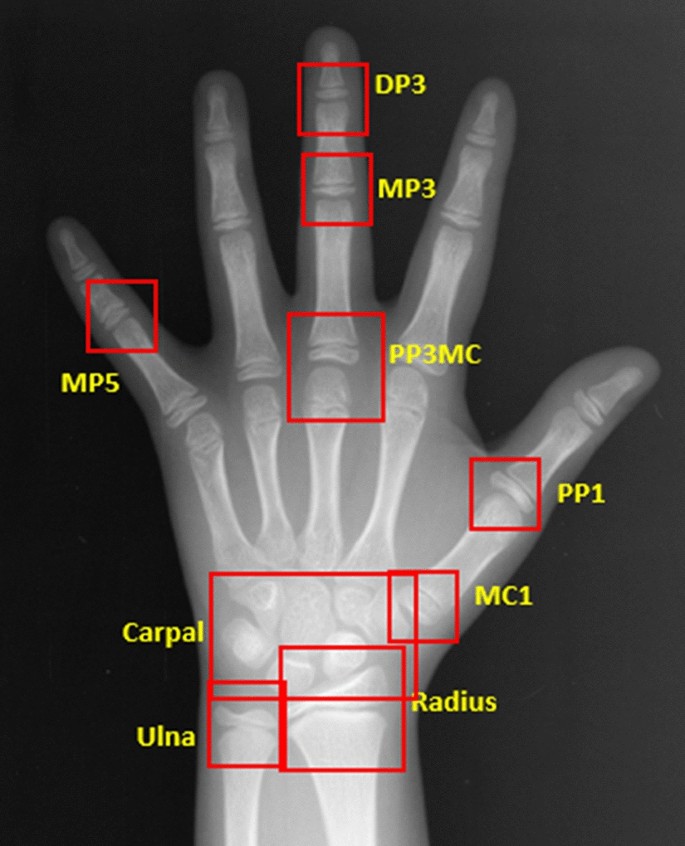

In addition to the major areas of growth plate evaluated for the TW3 method and the carpal region, all regions subject to the evaluation of SMI were included as ROIs (Fig. 2). In particular, MP5 (fifth middle phalanx) and PP1 (first proximal phalanx) were added by utilizing the detection algorithm based on the work by Li et al.13 RetinaNet, a deep convolutional neural network (CNN), was utilized for the automated detection of ROIs. Subsequently, each of the detected regions was analyzed for skeletal maturity level based on the morphological changes, such as epiphyseal widening, presence of sesamoid, epiphyseal capping and epiphyseal fusion. For image classification a vision transformer-based deep learning model was utilized. The final skeletal age was calculated by analyzing and integrating the probability of skeletal maturity of each area. Irrespective of the skeletal age prediction, skeletal maturity level of each of the six regions relevant for SMI evaluation was analyzed for SMI stage mapping. The final SMI stage was calculated by integrating the skeletal maturity and age of each ROI, and the final skeletal age. Both SMI and skeletal age were outputted as results (Fig. 3).

Automated detection of regions of interest. In addition to the ROIs used in the TW3 method, all of the six ROIs used for Fishman’s SMI, as well as the carpal bones are detected. (DP3, 3rd distal phalanx; MP3, 3rd middle phalanx; MP5, 5th middle phalanx; PP3MC, 3rd proximal phalanx/metacarpal; PP1, 1st proximal phalanx, MC1, 1st metarcarpal).